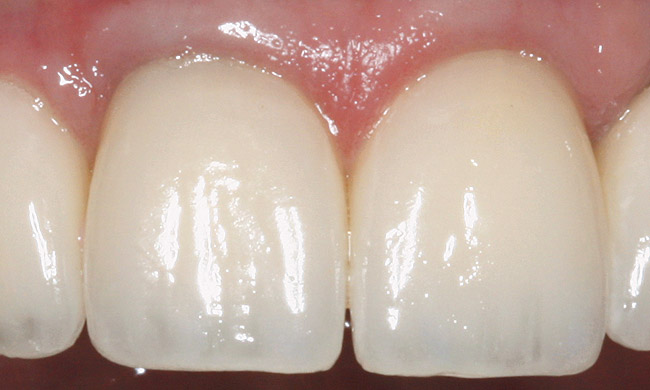

The esthetic parameters will be largely defined on how removal or retention of the tooth will affect the underlying bone and soft-tissue drape. There are two critical questions to consider. First, if the tooth is retained and surgery is necessary, will an esthetic result be possible? And second, if the tooth is removed, will the subsequent bone loss affect the soft-tissue drape negatively? This section will outline what is considered esthetic in the anterior portion of the dentition and will assume that deviation from this is considered “unesthetic.”

Tooth Proportions

Will the retention or removal of the tooth allow tooth proportions to be in the 75% to 86%36 height-to-width ratio? If the answer is yes, then proceed. If the answer is no, then orthodontic or periodontal procedures or both will need to be performed to place the tooth or the osseous crest in the correct esthetic position (Figure 15');" rel="imagepop" rem="#ip:figure14 and Figure 15">Figure 14 and Figure 15).

Gingival Margin Location/Symmetry

Will the removal or retention of the tooth allow gingival symmetry? Gingival symmetry is defined as an imaginary line that should be collinear, connecting the central incisors and canines and parallel with the interpupillary line or horizon if the interpupillary line is canted. Ideally, this line should also be parallel to the incisal edge and the curvature of the lower lip.37 The gingival margin of the lateral incisor should be even with or coronal to this line by a maximum of 3 mm (Figure 16).38 If these parameters are not met, then orthodontic or periodontal procedures or both will need to be performed to place the tooth in the correct esthetic position.